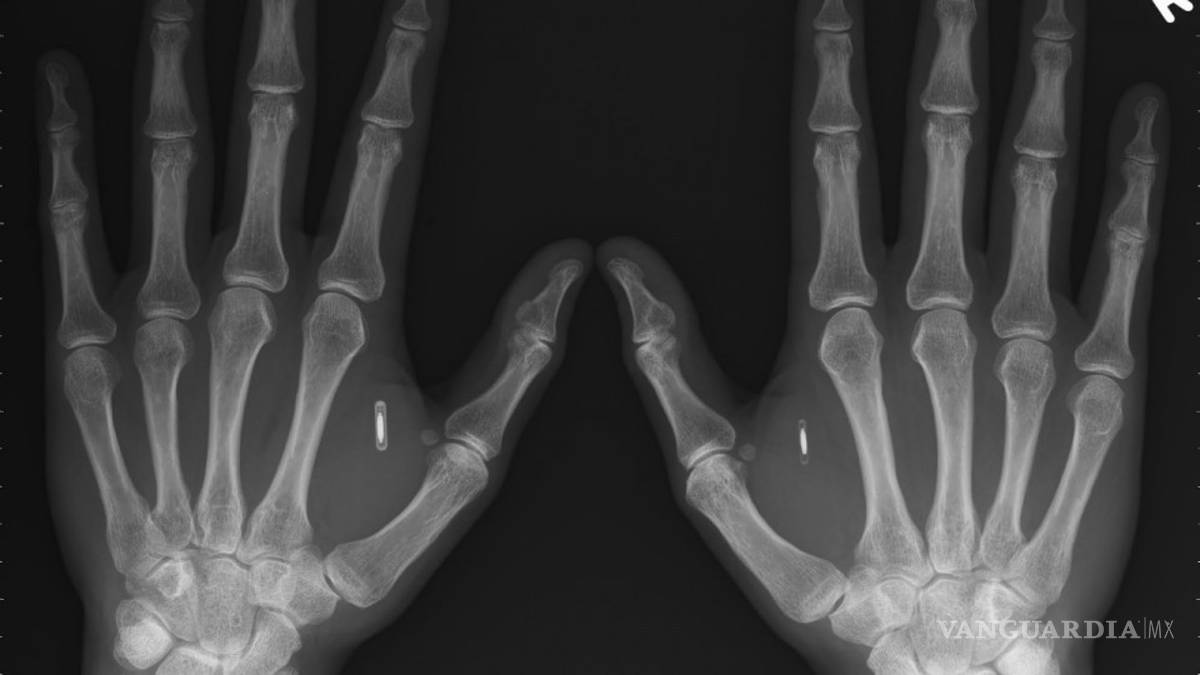

Casi cualquier parte de tu cuerpo puede usarse como forma de identificación. La disciplina que se encarga de medir un rasgo tuyo para darte entrada a ciertos datos se llama biometría.

Las principales formas implementadas o estudiadas incluyen reconocimiento de huellas dactilares, rostro, iris, voz y geometría de la mano.

Muchas otras modalidades se encuentran en distintas etapas de desarrollo y evaluación como el DNA, las orejas, la forma de escribir o caminar, las venas e incluso el olor.